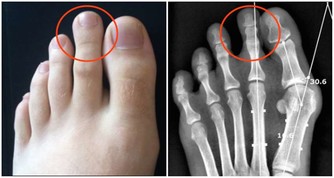

二、體內濕氣重的10大癥狀

1、嗜睡貪睡 2、大便溏瀉 3、舌苔厚膩 4、腹部肥胖 5、怠惰嗜卧 6、下肢沉重 7、脘腹脹滿 8、精力下降 9、情緒抑鬱10、痰多而粘。